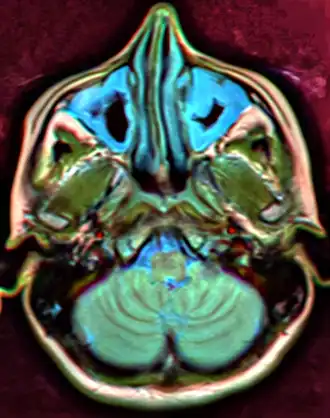

Chronic

For sinusitis lasting more than 12 weeks, a CT scan is recommended.[66] On a CT scan, acute sinus secretions have a radiodensity of 10 to 25 Hounsfield units (HU). In a more chronic state, they become more viscous, with a radiodensity of 30 to 60 HU.[69]

MRI image showing sinusitis. Edema and mucosal thickening appear in both maxillary sinuses. -